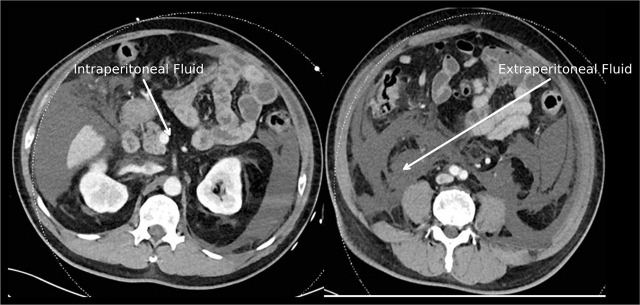

Case presentation: A 74-year-old male with diabetes and hypertension underwent HoLEP for a 180-ml prostate, during which 106 liters of normal saline irrigation were used over three hours. Intraoperatively, the patient developed sudden respiratory distress and hypotension, with arterial blood gas analysis revealing severe metabolic acidosis (pH 7.141, HCO3 11 mEq/L, Cl 115 mEq/L), primarily due to excessive saline absorption and hyperchloremia. The patient required intubation, vasopressor support, and emergency dialysis due to worsening hemodynamic instability. Postoperative imaging revealed intra-abdominal fluid collection, which was drained percutaneously. After two days of intensive ICU management, the acidosis resolved, and the patient was successfully extubated.